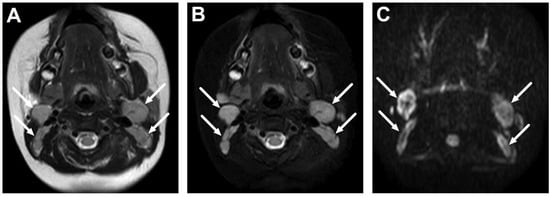

4.2. Retropharyngeal Abscesses and Suppurative Lymphadenitis